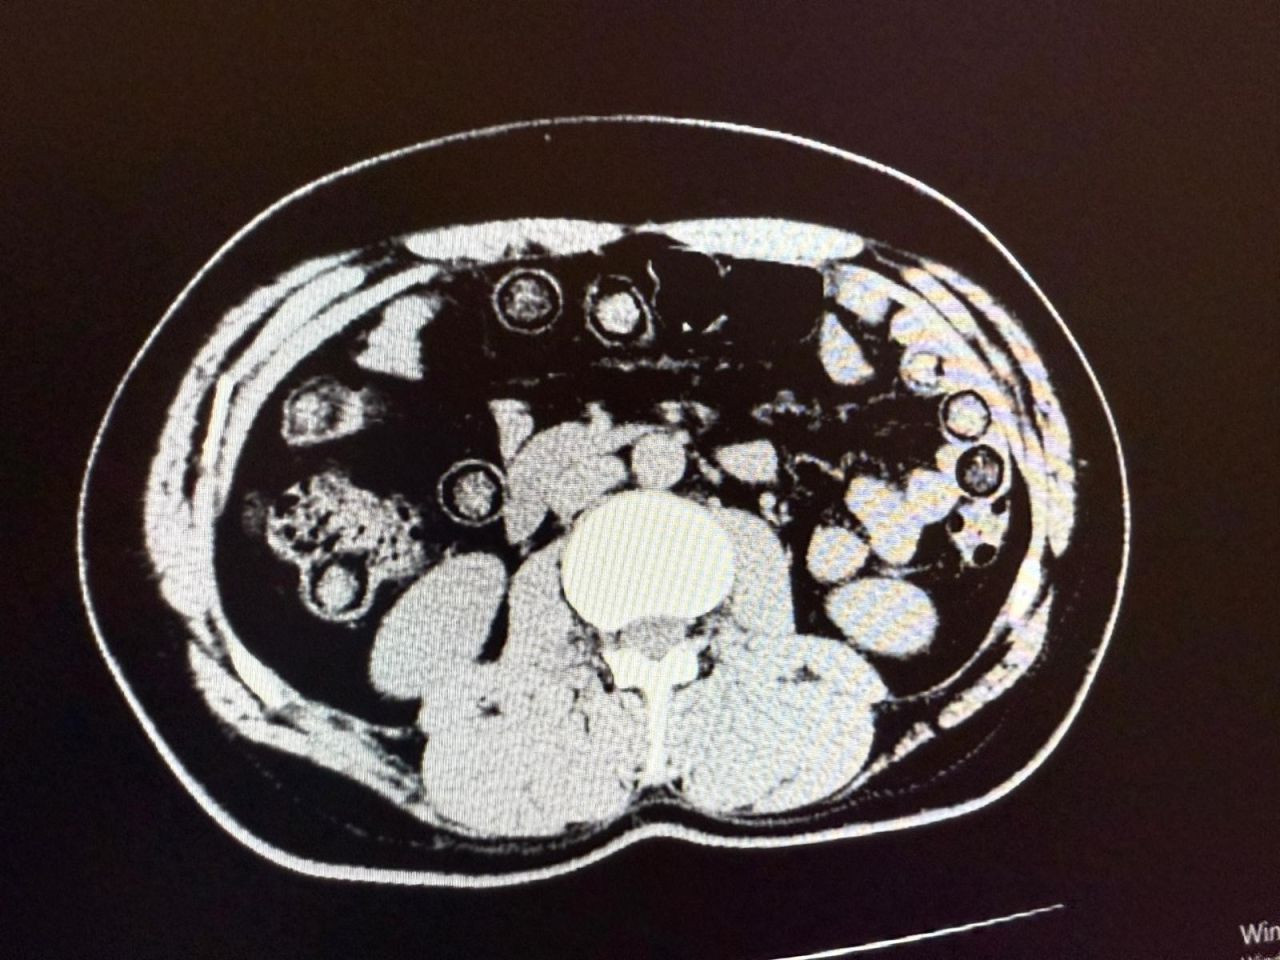

Hastanede yapılan tomografi görüntülerinde, şahısların midelerinde toplam 94 kapsül içinde 928 gram metamfetamin taşıdığı belirlendi. Kapsüller hastane ortamında çıkartılarak muhafaza altına alındı.